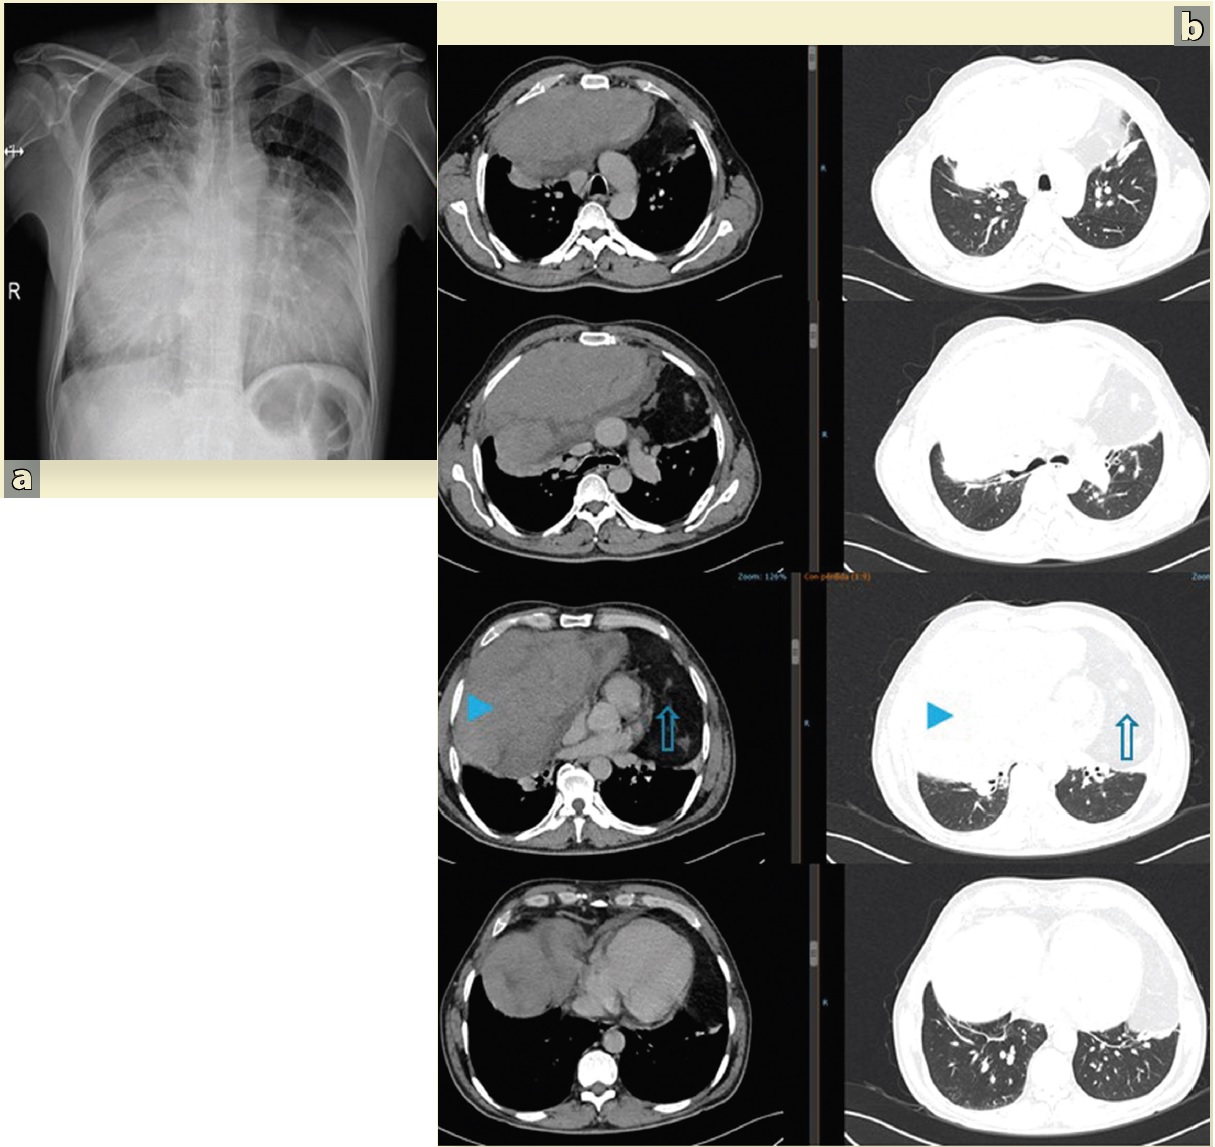

La radiografía y tomografia computarizada, suelen ser suficientes en el abordaje diagnóstico, tanto para dirigir la biopsia percutánea, como para la estrategia quirúrgica. En la radiografía de tórax (Figura 2a) lo usual es observar un ensanchamiento del mediastino o una sombra de alta densidad. La tomografía computarizada puede distinguir un tumor heterogéneo con densidad grasa, márgenes lisos o lobulados bien definidos, con desplazamiento de estructuras vasculares, nerviosas y bronquiales, sin adenopatías, de teratomas, fibromas, y quistes16,17. La presunción diagnóstica de la histología del sarcoma por tomografia computarizada alcanza 60% en centros especializados por las características típicas de la imagen (Figura 2b).

Hombre de 52 años de edad con disnea progresiva en los últimos 2 años. En los últimos meses presentó presión torácica y disfagia para sólidos. a) Radiografía de tórax. Lesión heterogénea con opacidad en los 2 tercios inferiores del tórax bilateral, b) TAC de tórax simple. Ventana mediastinal y pulmonar. En el mediastino anterior y hacia el lado derecho (cabeza de flecha) se identifica tumor sólido con zonas hipodensas en el interior de bordes definidos sin infiltración a otros órganos, el tumor con diámetro mayor de 21 cm con desplazamiento cardiaco a la izquierda. Otra lesión (flecha) heterogénea de 15 cm también en el mediastino anterior, lateralizado a la izquierdo adyacente a la grasa pericárdica, sugerente de liposarcoma.

Figura 2 Características radiológicas del sarcoma de mediastino anterior .